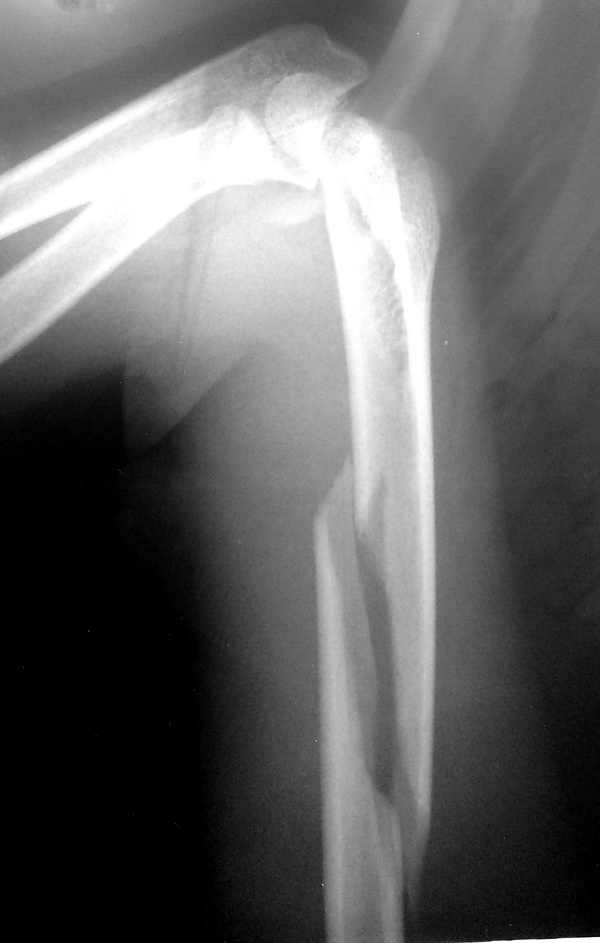

Рентгенограмма при переломе хирургической шейки плеча. Возможен перелом головки, отрыв малого или большого бугра, перелом анатомической и хирургической шейки плеча. Наиболее распространены переломы хирургической шейки, причём подавляющую часть пострадавших составляют люди пожилого возраста. Причиной перелома обычно становится падение на локоть, плечо или отведённую руку.

Пациент предъявляет жалобы на боли в области плечевого сустава. Вколоченные переломы сопровождаются нерезким отёком, болезненностью при попытке активных движений. Пассивные движения ограничены незначительно. При переломе со смещением клиническая картина более яркая. Пострадавшего беспокоят выраженные боли. Выявляется умеренный отёк, деформация области сустава и укорочение конечности. Определяется крепитация (хруст костных фрагментов). Диагноз уточняют по результатам рентгенографии.

При вколоченных переломах руку фиксируют специальной повязкой. При переломах хирургической шейки со смещением выполняют репозицию под местной анестезией. В последующем возможна фиксация повязкой по Турнеру или на отводящей шине, лейкопластырное или скелетное вытяжение. ЛФК назначают, начиная с 7-10 недели лечения. Срок иммобилизации составляет 6 недель.

Операция показана при нестабильных и оскольчатых переломах. Противопоказанием к операции является старческий возраст и тяжёлые хронические болезни.